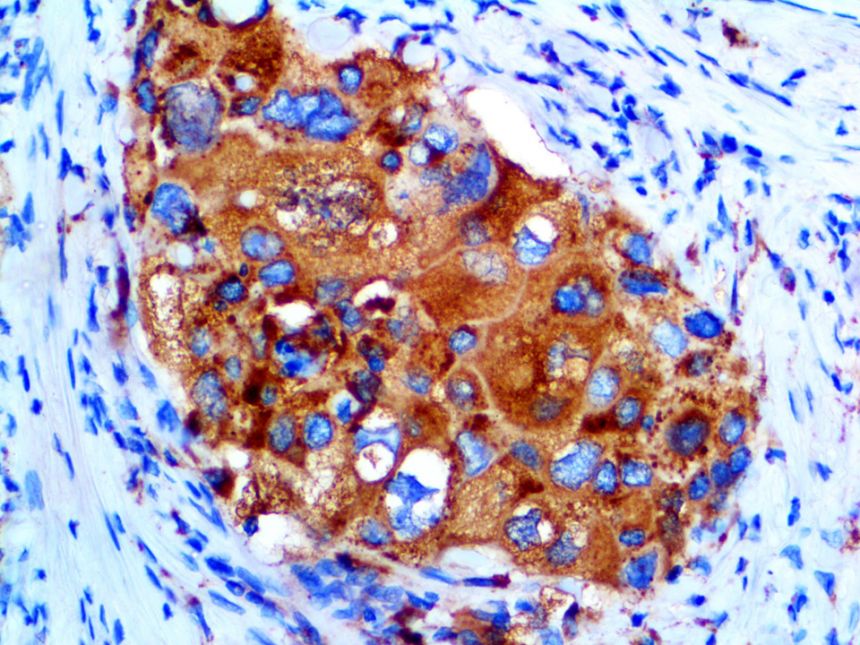

The first cytokines released are interleukin 1β (IL-1β) and tumor necrosis factor-α (TNF-α), which attract a variety of circulating white blood cells (WBCs) to the infection site, including neutrophils, monocytes, macrophages, and natural killer (NK) cells. This response, along with the antipathogenic chemicals released by these cells (i.e., complement), comprise the innate immune response. These cells directly attack the invading pathogen and also release additional cytokines, chief among them interleukin-1 and 6 (IL-6). IL-6 is essential for invoking the adaptive immune response, which calls T-cells, B-cells, and T helper (Th) cells to the infection site. IL-6 also stimulates further recruitment, proliferation and activation of macrophages.

It is the ICU physician who is most likely to witness one of the deadliest manifestations of the abnormal immunological response, the cytokine storm syndrome (CSS). This response is also referred to by some as the cytokine release syndrome (CRS). CSS is characterized by continuous activation and expansion of macrophage and lymphocyte populations, which secrete large amounts of cytokines, causing the cytokine storm. This massive cytokine release is akin to hemophagocytic lymphohistiocytosis (HLH) disease, a syndrome characterized by initial unchecked and persistent activation of cytotoxic T lymphocytes and NK cells.

This activation induces inflammatory monocytes to highly express IL-6, starting a localized and then systemic cascade effect that results in hyperproduction of IL-6, which accelerates the inflammatory process. Because IL-6 also increases vascular permeability, excessive levels cause blood vessels to become very leaky. This, along with clotting factors released from vascular endothelial cells, stimulates the coagulation cascade, resulting in microthrombosis (tiny clots), which leads to ischemia and tissue death of the kidney, intestines, heart, liver, brain and extremities.